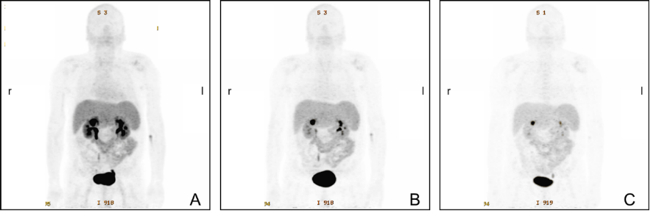

Peptide receptor RT (PRRT) has been recognised as a promising treatment for neuroendocrine (NET) patients. The use of 18F-FDG PET in NET is still controversial, whereas 68Ga-labelled somatostatin analogues are recognised radiopharmaceuticals. The long-term survival and efficacy of a second PRRT course with somatostatin analogues 177Lu-DOTATE in patients with advanced gastroenteropancreatic NET was evaluated (thesis of Kevin Winkler). Furthermore, the value of 18F-FDG PET/CT in these patients was assessed. Forty patients with GEP NET, who underwent two PRRT courses with 177Lu-DOTATATE and combined examinations with 68Ga-DOTA-TOC and 18F-FDG PET/CT, were evaluated (Fig. 5). After the second PRRT course, 2 patients (5.0%) were in partial remission, 21 patients (52.5%) experienced stable disease and 17 patients (42.5%) had progressive disease. The median overall survival was 122 months. After the second PRRT course, the median overall survival was significantly higher (P=0.033) in the 18F-FDG-negative group compared with the 18F-FDG-positive group (145.50 versus 95.06 months, respectively). The median time to progression was 19.37 months. In conclusion, a second PRRT course with 177Lu-DOTATE is an effective treatment approach for GEP NET patients with disease progression. A change in 18F-FDG status after PRRT may predict disease course and survival. Patients who are 18F-FDG negative have significantly longer overall survival than those who are 18F-FDG positive [12].